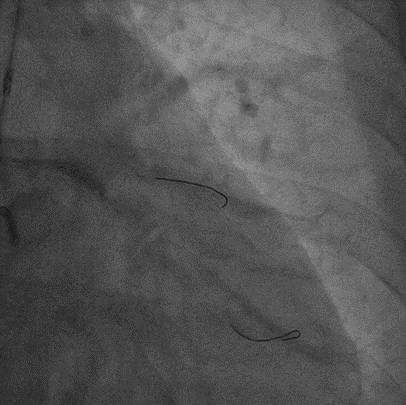

PCI过程

双侧造影,RCA 7F AL1.0,Runthrough导丝置于远端。

LCA 7F XB3.5,Cosair135,尝试Pilot200失败,进入假腔,Judo3成功通过闭塞段,换入Pilot150后,仍然进入假腔,再次使用Judo导丝,进入前降支远端,微导管造影,证实为真腔内,送入工作导丝。

Tip injection确认真腔,更换runthrough,2.0*20mm球囊预扩。

IVUS提示LAD近中段弥漫钙化,接近270度,钙化长度约26mm

LAD Stent 2.5*36mm,3.0*29mm ;Immediate image ,TIMI3

继续开通LCX,Pilot200 成功通过闭塞段,Tip injection 确认真腔

更换runthrough,Ballon dilatation 2.0*20mm,2.75*15mm

LCX Stent 2.5*36mm, Immediate image ,TIMI3

IVUS LCX-LM,RUN2

支架膨胀、贴壁良好,LCX开口MSA 5.68mm²,LM MLA 5.67mm²。

NC 3.0*15mm,3.5*15mm后扩张;LM stent 4.0*19mm

Runthrough 掏LCX支架网眼,退LAD导丝,送入 NC 3.5*15mm扩张,优化开口支架形态

IVUS LAD-LM,RUN3,LAD口部MSA 9.03mm²,LM MSA 10.18mm²

NC Ballon dilatation 3.0*15mm,3.5*15mm,4.0*12mm

Final result